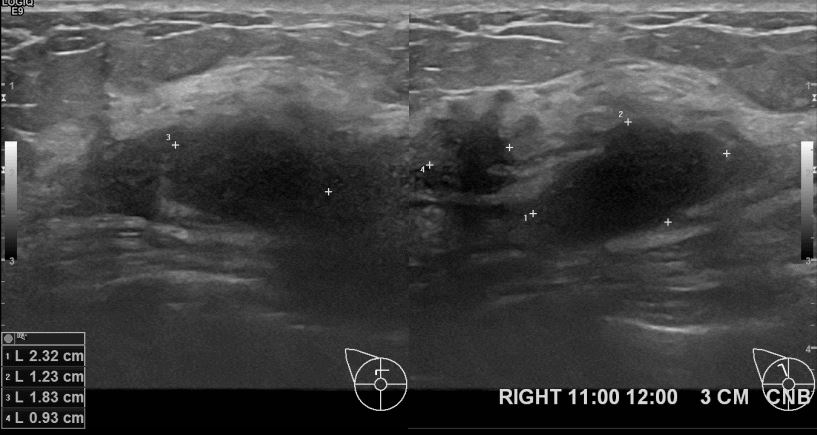

아산유외과개원후 643번째 유방암진단

상기환자 외부검사상 이상소견으로 내원하신 50대여성으로 우측 유방의 의심스러혹

조직검사시행해 유방암 진단되었읍니다